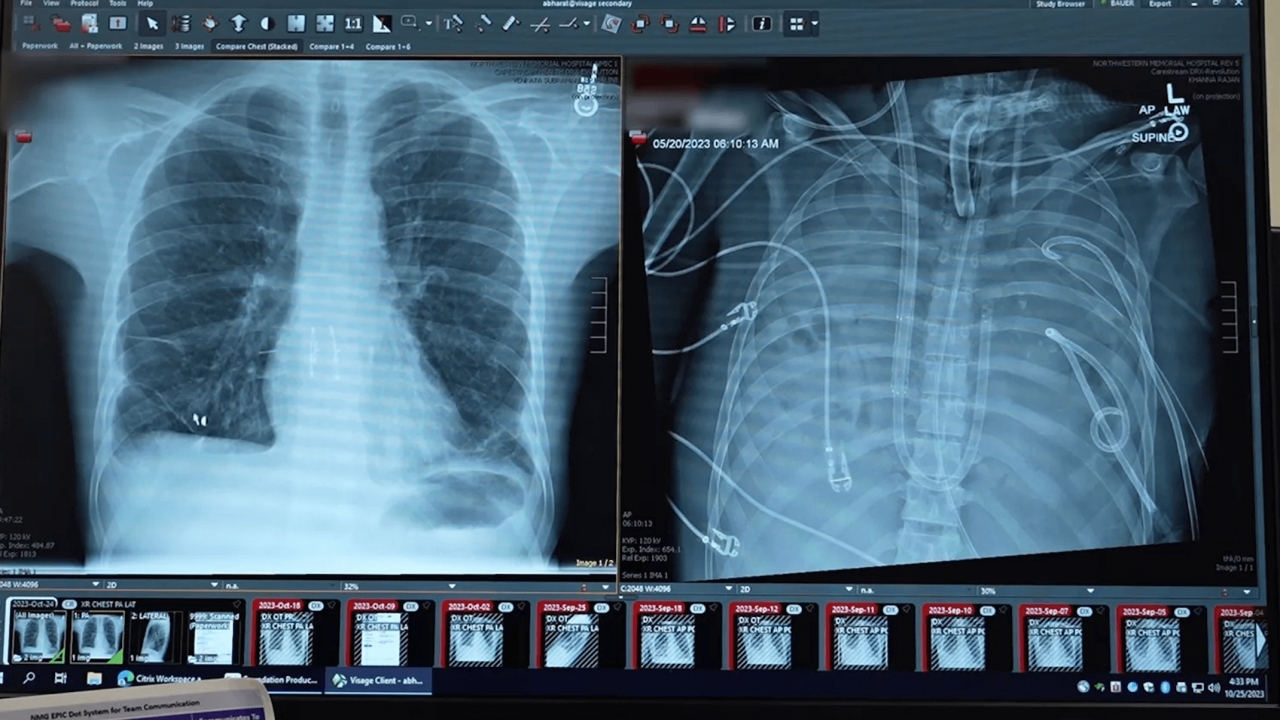

Man receives first whole eye transplant after losing half his face